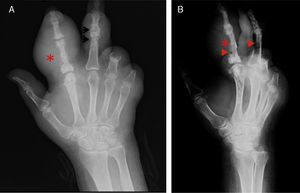

A) Radiografía dorsopalmar de mano izquierda. B) Radiografía lateral de mano izquierda. En ambas se aprecia aumento de volumen en tejidos blandos en segundo y tercer dedo correspondientes con tofo (*), en los tejidos óseos resalta la presencia de erosiones en borde colgante (flechas), con pérdida de espacio articular.

Caso clínicoVarón de 46 años de edad con antecedentes de hiperuricemia, amputación traumática del 4.° y 5.° dedos de la mano izquierda y gota tofácea crónica durante 8 meses automedicado con glucocorticoides. Fue ingresado con historia de 12 días de presentar aumento de volumen en segundo dedo mano izquierda, agregándose dolor, hiperemia y salida de material de aspecto purulento. A la exploración física se encontraron tofos en ambos codos, manos y pies en superficies extensoras y flexoras, el más grande abarcaba la totalidad del segundo dedo izquierdo (fig. 1). Al ingreso, los niveles de ácido úrico y cortisol fueron de 10,4mg/dl y 10,39mg/dl, respectivamente; la eTFG fue de 11,96ml/min3. El material exudativo encontrado en los tofos, mediante aspiración por aguja, fue analizado en microscopía con luz polarizada, revelando abundantes cristales de urato monosódico y escasos leucocitos (fig. 2). Los cultivos del aspirado se reportaron negativos para crecimiento bacteriano. En las radiografías de mano se observaron erosiones óseas típicas de gota (fig. 3).